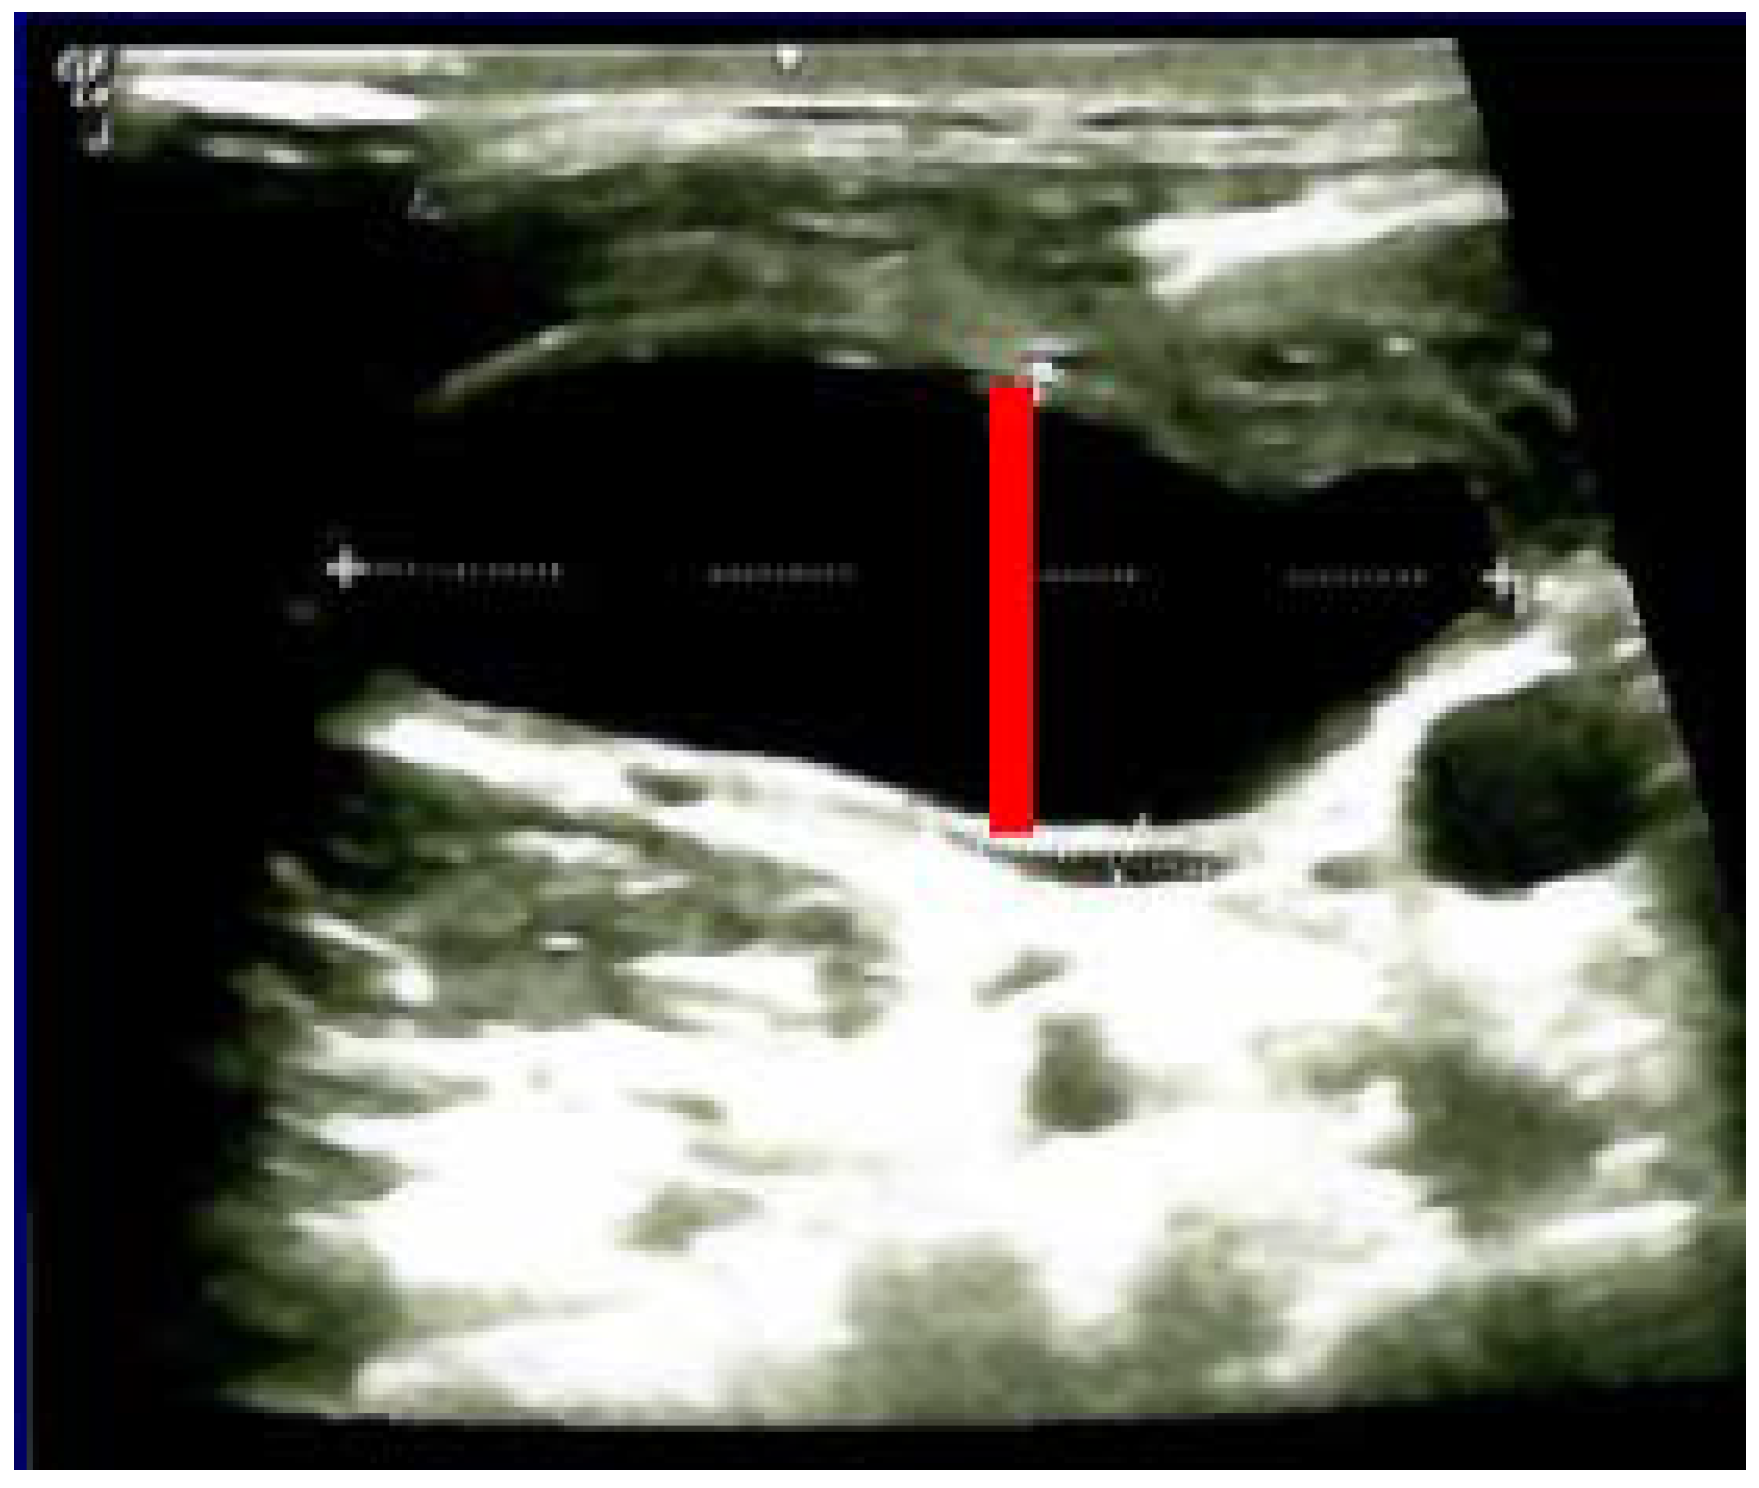

The diagnostic of HS was established after she was seen by different specialists as outpatient; she started local therapy with artificial tears and local nasal products with no significant improvement. In the meantime, a right neck swelling was progressively increasing, thus she was re-admitted 5 weeks since thyroidectomy. Neck ultrasound revealed a hypoechoic cystic-like area at the level of right lateral cervical level (of 60 mm maximum diameter) without thyroid remnants or local lymph node enlargement. (Figure 2).

Figure 2.

Neck ultrasound (right lateral area): hypoechoic, cystic- like, well-shaped mass of 6 by 2 by 4.5 cm (post-thyroidectomy capture: after 5 weeks since surgery before any additional intervention; red line represents the limits of the mass).

Ultrasound—guided fine need aspiration of the right mass provided cvasi-complete reduction of the liquid with stationary ultrasound features after 90 min. The liquid examination showed mature lymphocytes, rare erythrocytes, rare cholesterol crystals, lymph fluid, consistent with the diagnostic of lymphocele. A mild clinical improvement of HS—associated features was registered, but within 2 days, the neck mass rapidly regrew, and the patient was re-admitted. Under local anesthesia, there was a liquid evacuation (macroscopic aspect with milky-like aspect, a volume of 5–6 mL) and a drain tube was placed for 4 days. Ultrasound aspects showed a progressive regression of the right cystic mass with improvement of HS which slowly remitted within the next 2–3 months. (Figure 4).

Figure 4.

The evolution of within following weeks after thyroid surgery ultrasound features. (A). Right neck ultrasound aspect at the moment of fine needle aspiration (5 weeks since surgery)—on the right and 6 days after fine needle aspiration procedure (after cvasi-complete evacuation, the cystic mass relapsed within 48 h)—on the left. (B). Right neck ultrasound within the first day of tube drainage (6 weeks since initial surgery) showing a massive reduction of the cystic mass. (C). Drainage tube was removed after 4 days. Post-thyroidectomy scar and post-tube removal aspect. (D). Right neck ultrasound after 2 weeks from removing the drainage—persistent cystic mass, but with progressive improvement of HS (approximately 9 weeks since initial surgery). (E). Right neck ultrasound after another 2 weeks from removing the drainage –progressive reduction of cystic mass, but with remarkable improvement of HS (approximately 11 weeks since initial surgery). (F). Scar aspect 12 weeks since surgery and 5 weeks since lymphocele drainage. (G). Recovery of HS—approximately 8 weeks since drainage. (H1,H2). Bilateral neck ultrasound 20 weeks since thyroid surgery showing regression of the lesions on both sides versus prior examinations. (H1). Right later-cervical cystic collection of 2 by 2.8 by 0.9 cm (2.5 mL) and peripheral areas of fibrotic reorganization. (H2). Left later-cervical hypoechoic, inhomogeneous mass (no vascular signal) showing fibrotic reorganization (0.25 mL).